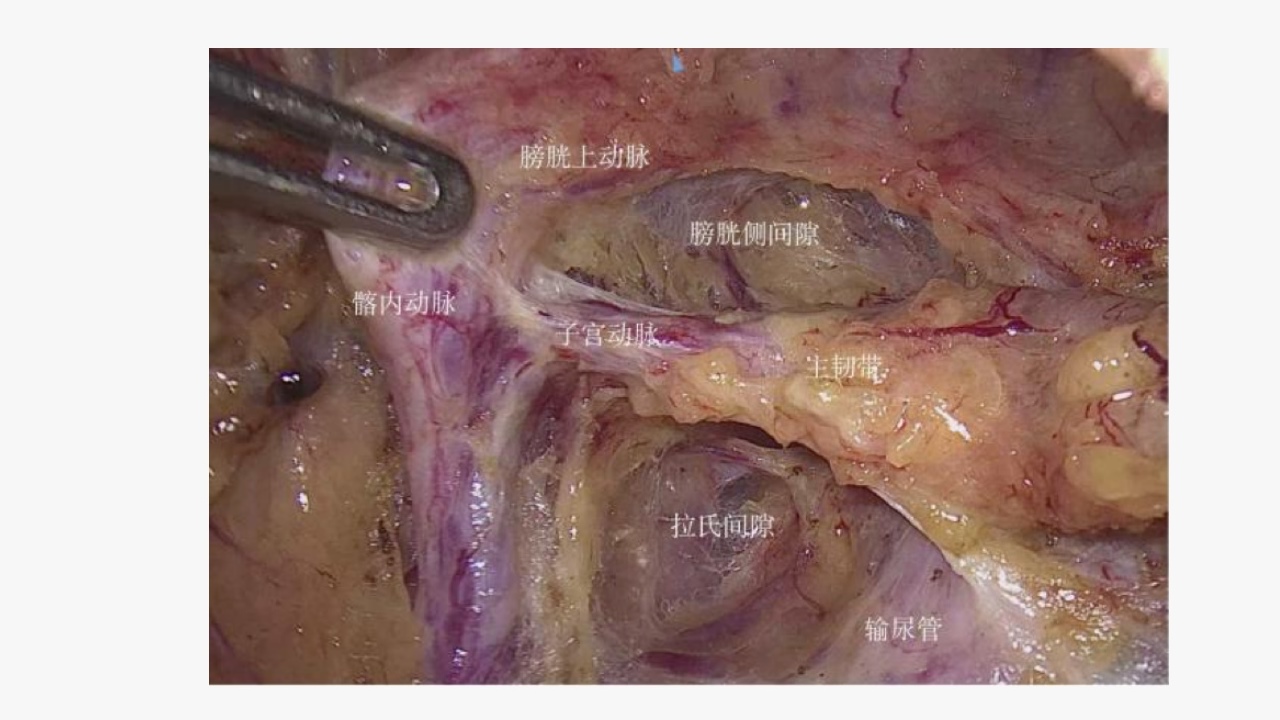

对于膀胱侧间隙(图3),需要强调的是一定是位于膀胱上动脉和子宫动脉之间,外侧界为髂内动脉,底部为盆隔上筋膜,内侧界为膀胱外侧的膀胱宫颈血管(图4,5)或者输尿管为界(视频1),图4、图5显示分离膀胱侧间隙时,内侧边界以膀胱宫颈血管为界,也可以离断该血管,以输尿管外侧为界;膀胱宫颈血管常呈网状分布且变异较多,建议不必强行在分离该间隙时离断该血管,以免增加出血风险,遵循“见到而不离断”原则即可。

个人观点间隙分离的目的仅在于输尿管的游离和拟切除韧带的暴露,别无其他。比如,分离膀胱侧间隙的目的在于游离主韧带的前侧、膀胱宫颈韧带或输尿管(膀胱宫颈韧带处)的外侧(图1);分离拉氏间隙的目的在于游离输尿管的腹侧、主韧带的背侧、骶韧带的外侧,以此类推,每个间隙的分离都是围绕输尿管的游离和韧带的暴露切除进行的。